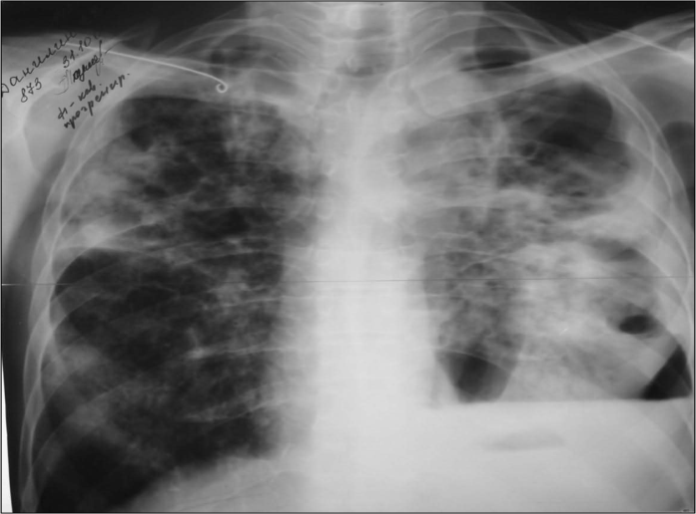

Тамағының ауырғаны, дауысының қарлыққаны, шырышты қақырықты жөтел, әлсіздік, тершендік, 4-5кг жүдеу 42 жастағы Н. науқасты мазалайды. Кеуде торша ағзаларының рентгенограммасына қараңыз:

Мүмкін болатын болжам диагнозды таңдаңыз:

А) Фиброзды-кавернозды туберкулез, шашырау фазасы

В) Кавернозды туберкулез, себінді фазасы

С) Жедел диссеминирлі туберкулез

D) Жеделдеу диссеминирлі туберкулез

Е) Созылмалы диссеминирлі туберкулез

{Дұрыс жауап}= D